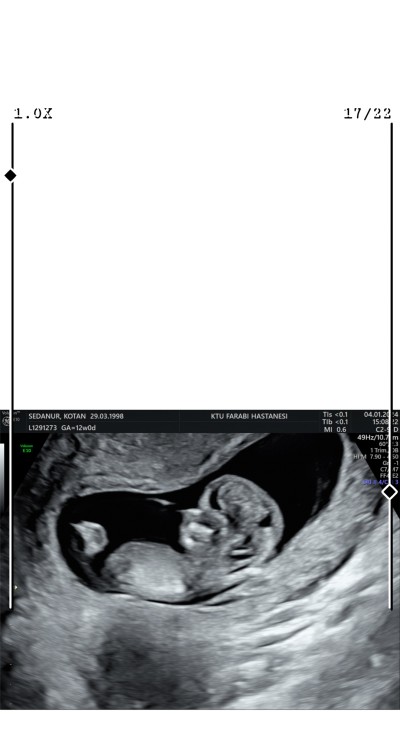

Cinsiyet tahmini yapabilirmisini,

Cinsiyet tahmini alablirmiyim

Gebelik haftası

13

Kız Bebek bence fotodan bişey anlamadım bebek olduğu bile orda zor anlaşılıyor:)) hissime göre söyledim

Bu erekk bebebk kızlar düz bkara yukarıya doğru erkkler önlere doğru bakar

Yok kız bebek bu ben nerde görsem tanırım:)))

Sizin bebegininz sanki kız gibi duruşu

Bende kıza benzettim sanki